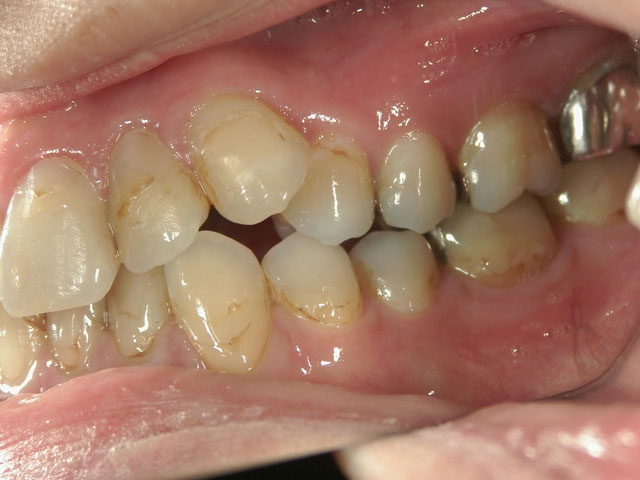

矯正歯科 治療前矯正歯科 治療前

矯正歯科 治療前 外科手術併用(コルチコトミー)、非抜歯

no.7_6967_治療前_右_01.jpgno.7_6967_治療後_正面_01.jpgno.7_6967_治療前_左_01.jpg